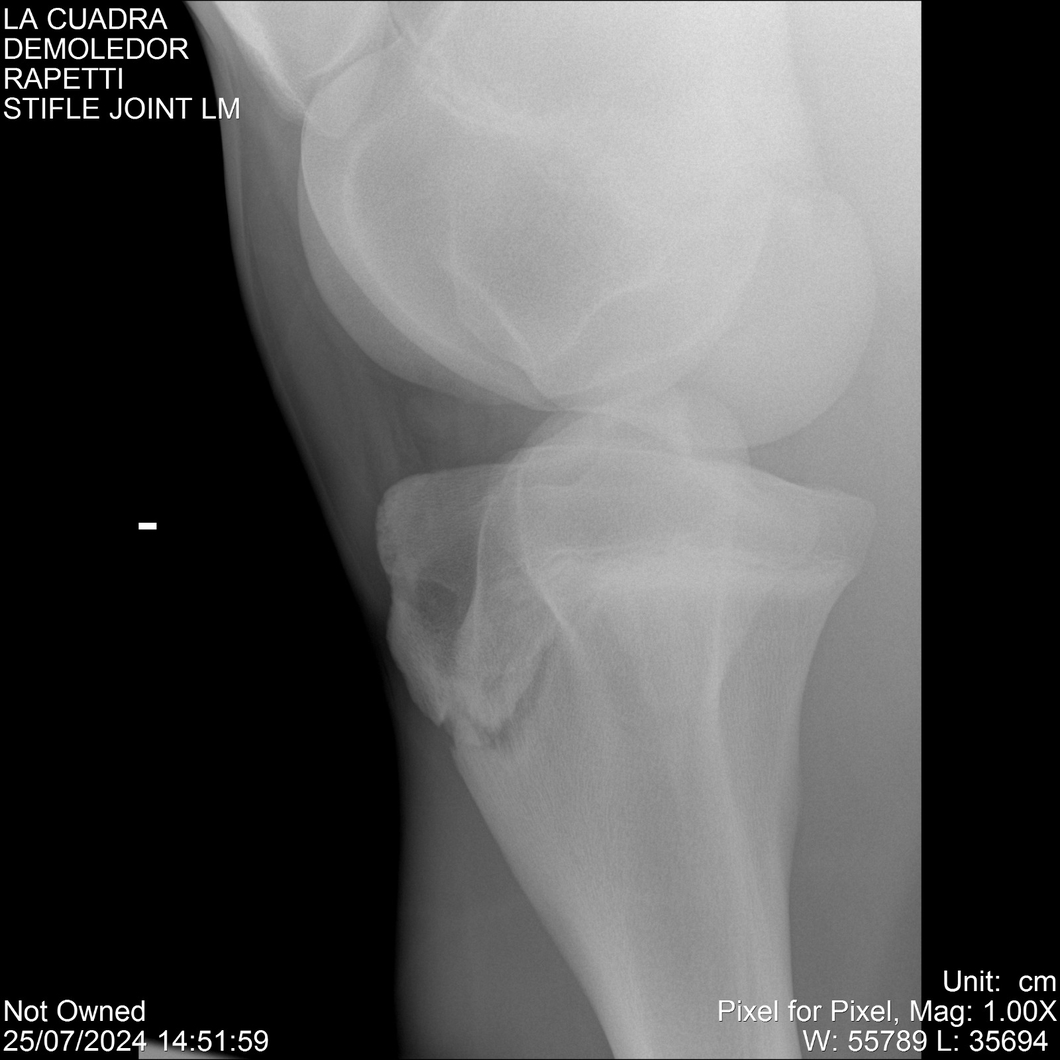

LOTE 14, DEMOLEDOR 🔥 🔥 🔥 Lote Anterior Volver al remate Lote Siguiente Ficha Contacto Montevideo - Ficha del Lote Identificador: #284454 Categoría: Yeguarizos Montevideo - 89 Visualizaciones ClicData Contacto Empresa: Abelenda N. R., Walter Hugo Nombre*: Teléfono* : E-mail* : Mensaje Enviar Registrese gratis Este contenido Exclusivo está disponible sólo para usuarios registrados Ingresar